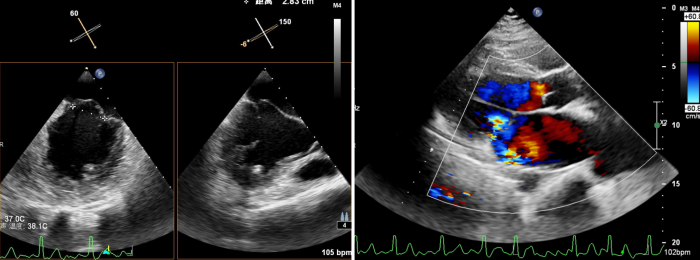

术前,超声科聂红军教授运用全数字化高端心脏彩色多普勒诊断仪,为患者进行食道三维超声综合评估,确定了二尖瓣返流量及返流分区。同时,在手术中实时监测二尖瓣瓣叶返流区与钳夹器的位置是否吻合,术后还可即刻探查二尖瓣返流量减少情况,如果把手术比作开车,那超声科就是手术的导航系统。

术中,蒋路平主任团队在经食道超声引导下通过股静脉穿刺房间隔将二尖瓣钳夹系统送入患者左心房到达二尖瓣口,然后医生全程在经食道超声引导下通过评估二尖瓣返流位置以及返流程度等精准夹合二尖瓣叶,整个过程都是在心脏不停跳的情况下完成。

术前心脏彩超所示:二尖瓣返流